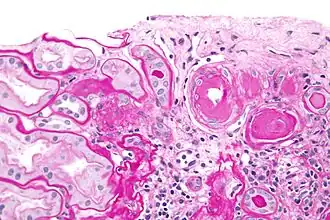

Hyaline cartilage is named after its glassy appearance on fresh gross pathology.[3] On light microscopy of H&E stained slides, the extracellular matrix of hyaline cartilage looks homogeneously pink, and the term "hyaline" is used to describe similarly homogeneously pink material besides the cartilage. Hyaline material is usually acellular and proteinaceous. For example, arterial hyaline is seen in aging, high blood pressure, diabetes mellitus and in association with some drugs (e.g. calcineurin inhibitors). It is bright pink with PAS staining.